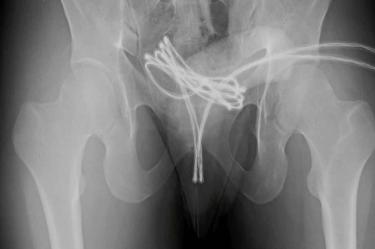

Los estudios de imagen revelaron que el cable había alcanzado su vejiga, lo cual dificultó el procedimiento de extracción. Los médicos optaron por realizar una intervención quirúrgica bajo anestesia general, utilizando una cámara insertada por la uretra para poder retirar el objeto con el menor daño posible.